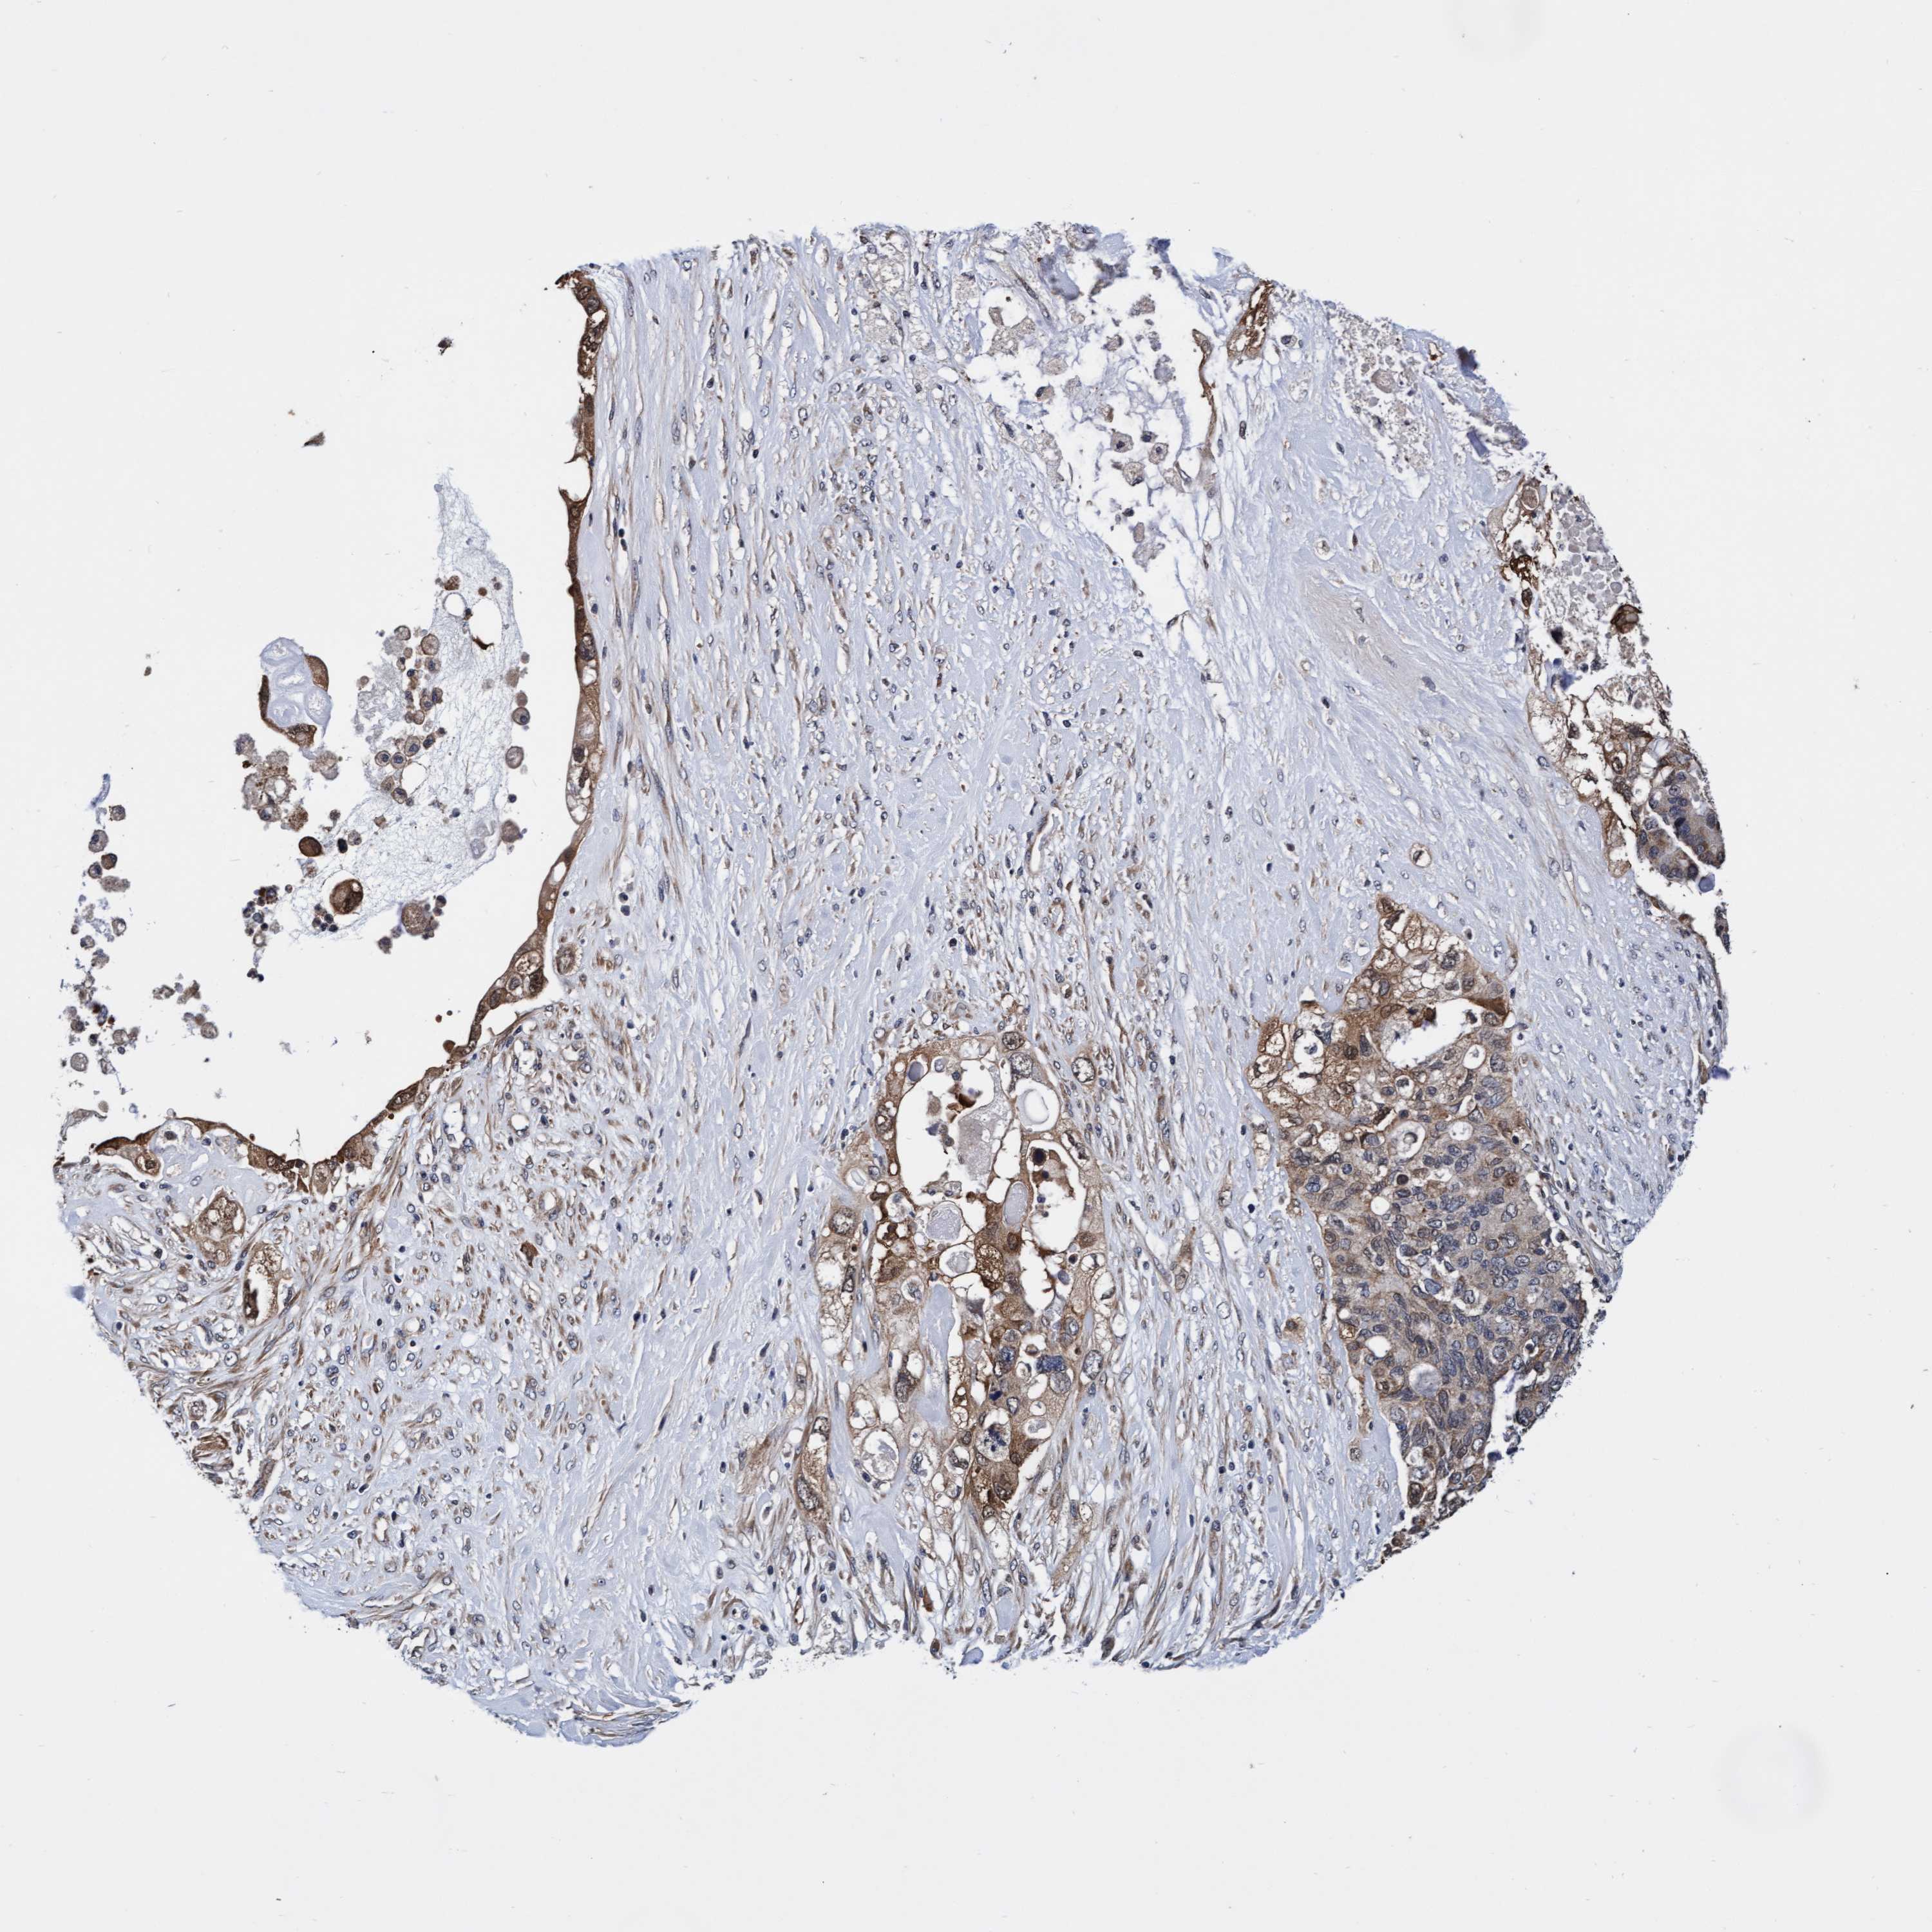

PANCREATIC CANCER - Protein expressioni

A mouse-over function shows sample information and annotation data. Click on an image to view it in a full screen mode. Samples can be filtered based on level of antibody staining by selecting one or several of the following categories: high, medium, low and not detected. The assay and annotation is described here.

Note that samples used for immunohistochemistry by the Human Protein Atlas do not correspond to samples in the TCGA dataset.

Antibody stainingi

Antibody staining in the annotated cell types in the current human tissue is reported as not detected, low, medium, or high, based on conventional immunohistochemistry profiling in selected tissues. This score is based on the combination of the staining intensity and fraction of stained cells.

Each image is clickable and will lead to virtual microscopy that enables deeper exploration of all samples and also displays staining intensity scores, fraction scores and subcellular localization as well as patient and tissue information for each sample.

Antibody HPA021633

Antibody HPA023249

Antibody HPA026561

Antibody CAB002501

Adenocarcinoma, NOS

Adenocarcinoma, metastatic, NOS